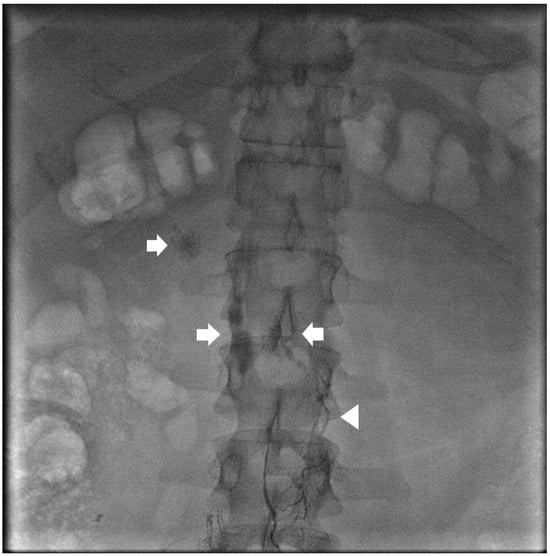

Figure 3. Spot image from an intra-nodal lymphangiogram for a 59-year-old patient with traumatic chylothorax after esophagectomy. Bilateral 25 G needles (arrows) are used to inject lipiodol into the inguinal lymph nodes and up the lymphatic vessels (arrow heads).

Figure 4. Spot image from the same patient in Figure 3 showing lipiodol within the thoracic duct (arrow) and coils at the distal thoracic duct (arrowhead) to address a leak in the mediastinum (star).